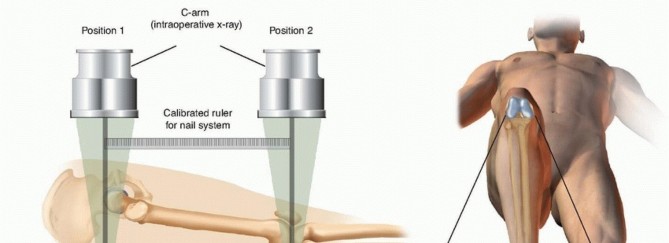

Nail lengths are often determined intraoperatively but can be ascertained by imaging the contralateral femur. Radiographs are evaluated to determine the location and morphology of the fracture; they should be scrutinized for nondisplaced secondary fracture lines that could become displaced during operative treatment. Occasionally, fracture fragments may be stuck in the canal and may need to be pulled out. In the case of fractures that show significant shortening preoperatively, it may be difficult to restore length off the fracture table. A trial reduction should be performed under fluoroscopy before the start of the procedure; the patient must be paralyzed for the procedure. If length is difficult to restore manually, then a femoral distractor should be used for the procedure. Placement of the femoral distractor is described in the section on Fracture Reduction. Before preparing and draping the injured limb, the surgeon should examine the contralateral extremity to determine the patient's normal leg length and rotation. Femoral length can be evaluated by using a radiographic ruler and intraoperative fluoroscopy ( FIG 7A). Normal rotation can be determined by flexing the hip and knee and checking the patient's normal internal and external rotation of the hip and by examining the normal resting position of the foot as the patient lies supine on the operating room table ( FIG 7B).  ---

---  ### FIG 7 • A. Schematic lateral view of a patient on a radiolucent operating room table, depicting how to use a radiopaque ruler and fluoroscopy to determine femoral length. B. Schematic anterior view of a patient on the operating room with the uninjured hip and knee flexed, checking the patient's normal internal and external rotation of the hip.

### FIG 7 • A. Schematic lateral view of a patient on a radiolucent operating room table, depicting how to use a radiopaque ruler and fluoroscopy to determine femoral length. B. Schematic anterior view of a patient on the operating room with the uninjured hip and knee flexed, checking the patient's normal internal and external rotation of the hip.